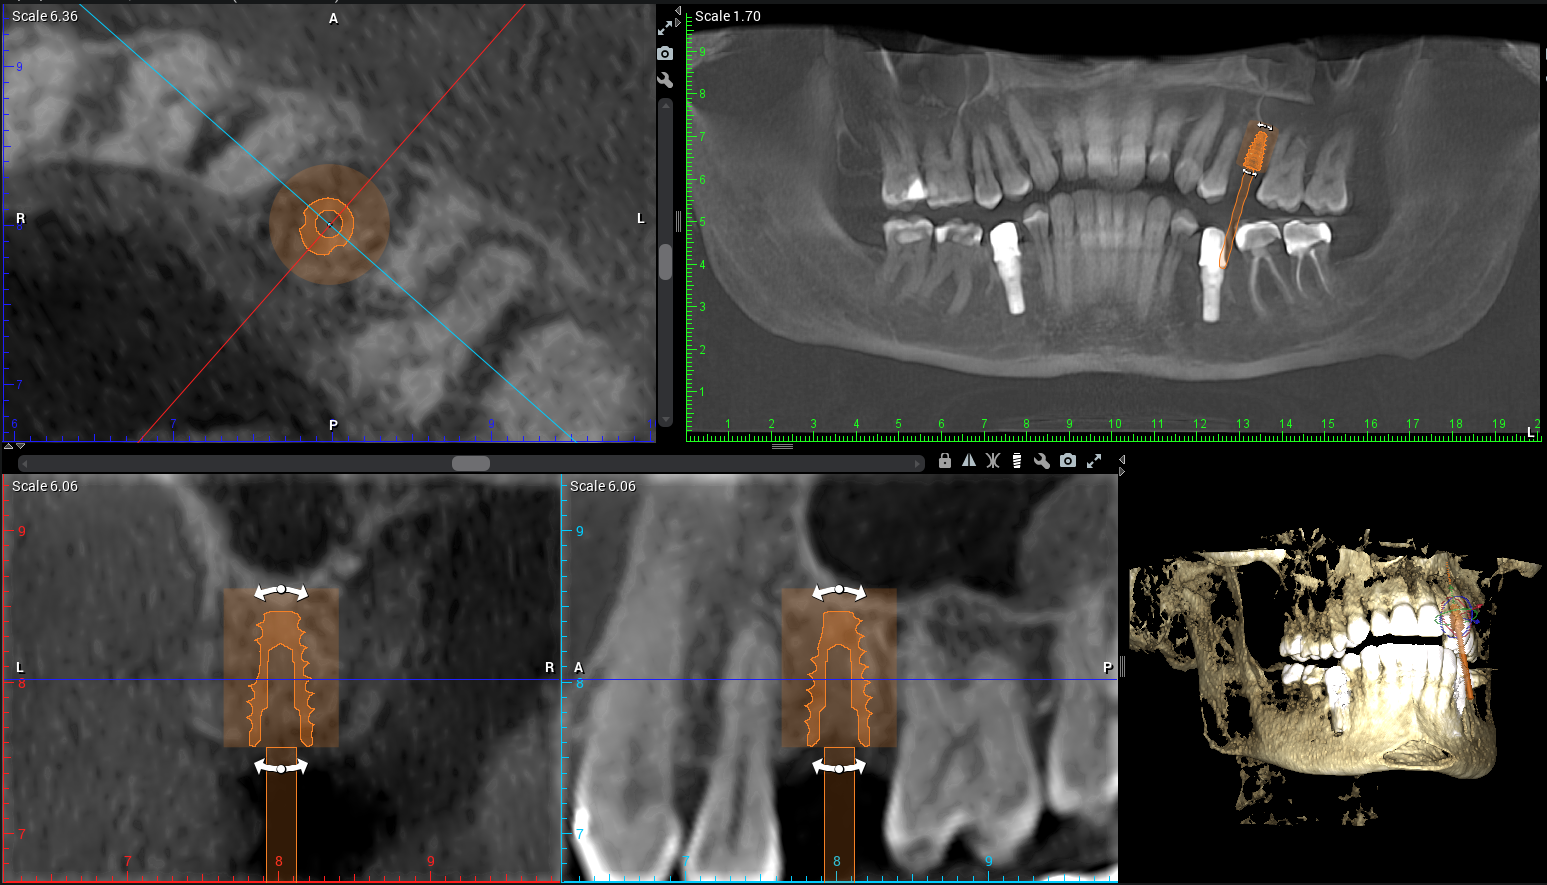

At Teuscher Legacy Dental, every implant case is planned with 3D cone beam CT imaging and digitally designed surgical guides — the same technology used by other leading surgical centers.

This allows us to:

Visualize bone quality, and sinus anatomy, and nerve locations

Place implants with extreme precision

Often shorten healing time and improve comfort

Optimize location of future crown (the chewing part of the implant)

(Source: Vercruyssen et al., Clin Oral Implants Res 2014;25:94–99)

This first step also helps make sure the patient is on the same page with what to expect a final result to look like. We also go over financial details and timeline. This way the patient knows what to expect every step of the way!CBCT 3D Planning

Before taking any teeth out or diving into implant placement, we start with a CBCT scan to evaluate the bone structure in 3D. This shows us the height, width, and quality of bone, and how close we are to adjacent roots or anatomical structures. Planning the exact implant location here prevents complications later.Site Preparation & Grafting (if needed)

CBCT imaging allows us to measure bone density, identify vital structures (like nerves and sinuses), and plan the exact position of your future implant.

Using digital treatment planning, we design a custom surgical guide to ensure the implant is placed with millimeter accuracy.

Example of Teuscher Legacy Dental’s 3D implant Planning Software

3D scans (CBCT imaging) and digital planning lead to better fit, healing, and long-term success. A 2D X-Ray is less expensive, but also doesn’t allow for the same precision in planning where the implant post will sit in your jawbone. Sometimes, a dentist will use the 3D scan to generate a surgical guide, which allows for even greater precision when surgically placing the post.